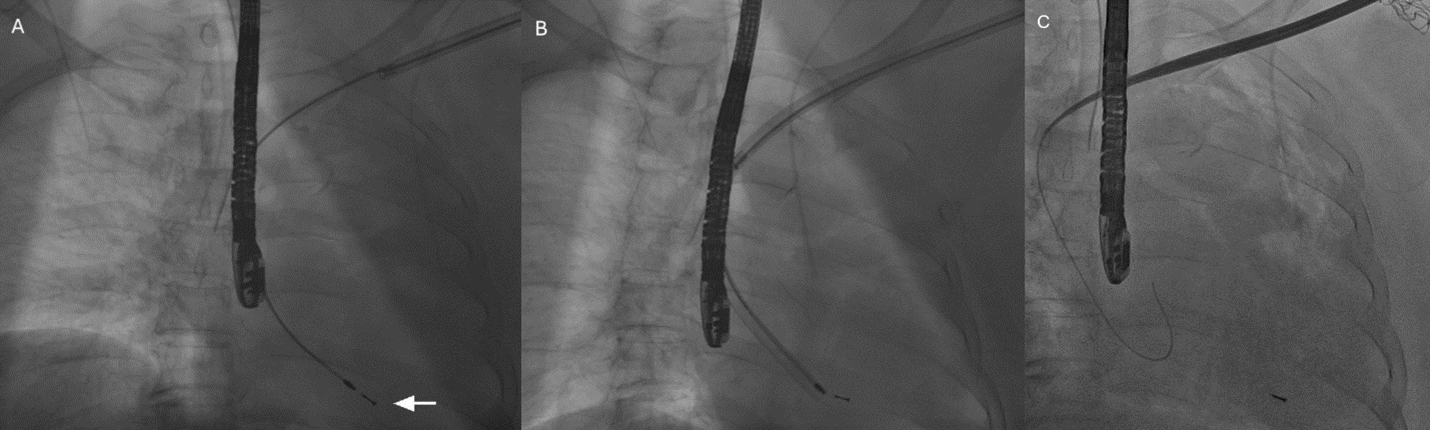

A 70-year-old woman with dementia, history of sick sinus syndrome, and permanent atrial fibrillation previously underwent dual-chamber transvenous pacemaker implantation. Over time, she developed Twiddler’s syndrome with repeated generator manipulation, resulting in diaphragmatic capture and recurrent pocket complications. The pacemaker system on the left side was extracted (Figure A-C). Intraoperative transesophageal echocardiogram was used to monitor potential lead extraction complications.

The AVEIR delivery sheath was advanced only to the distal subclavian vein to avoid vascular injury. The steerable delivery catheter was then advanced through the sheath with the protective sleeve in place and directed across the tricuspid valve into the right ventricle (Figure D and E). The device was actively fixed along the septum, and biplane fluoroscopy with contrast injection confirmed stable positioning and adequate myocardial engagement (Figure F; Videos 1-3). Electrical testing demonstrated satisfactory pacing thresholds, sensing, and impedance.